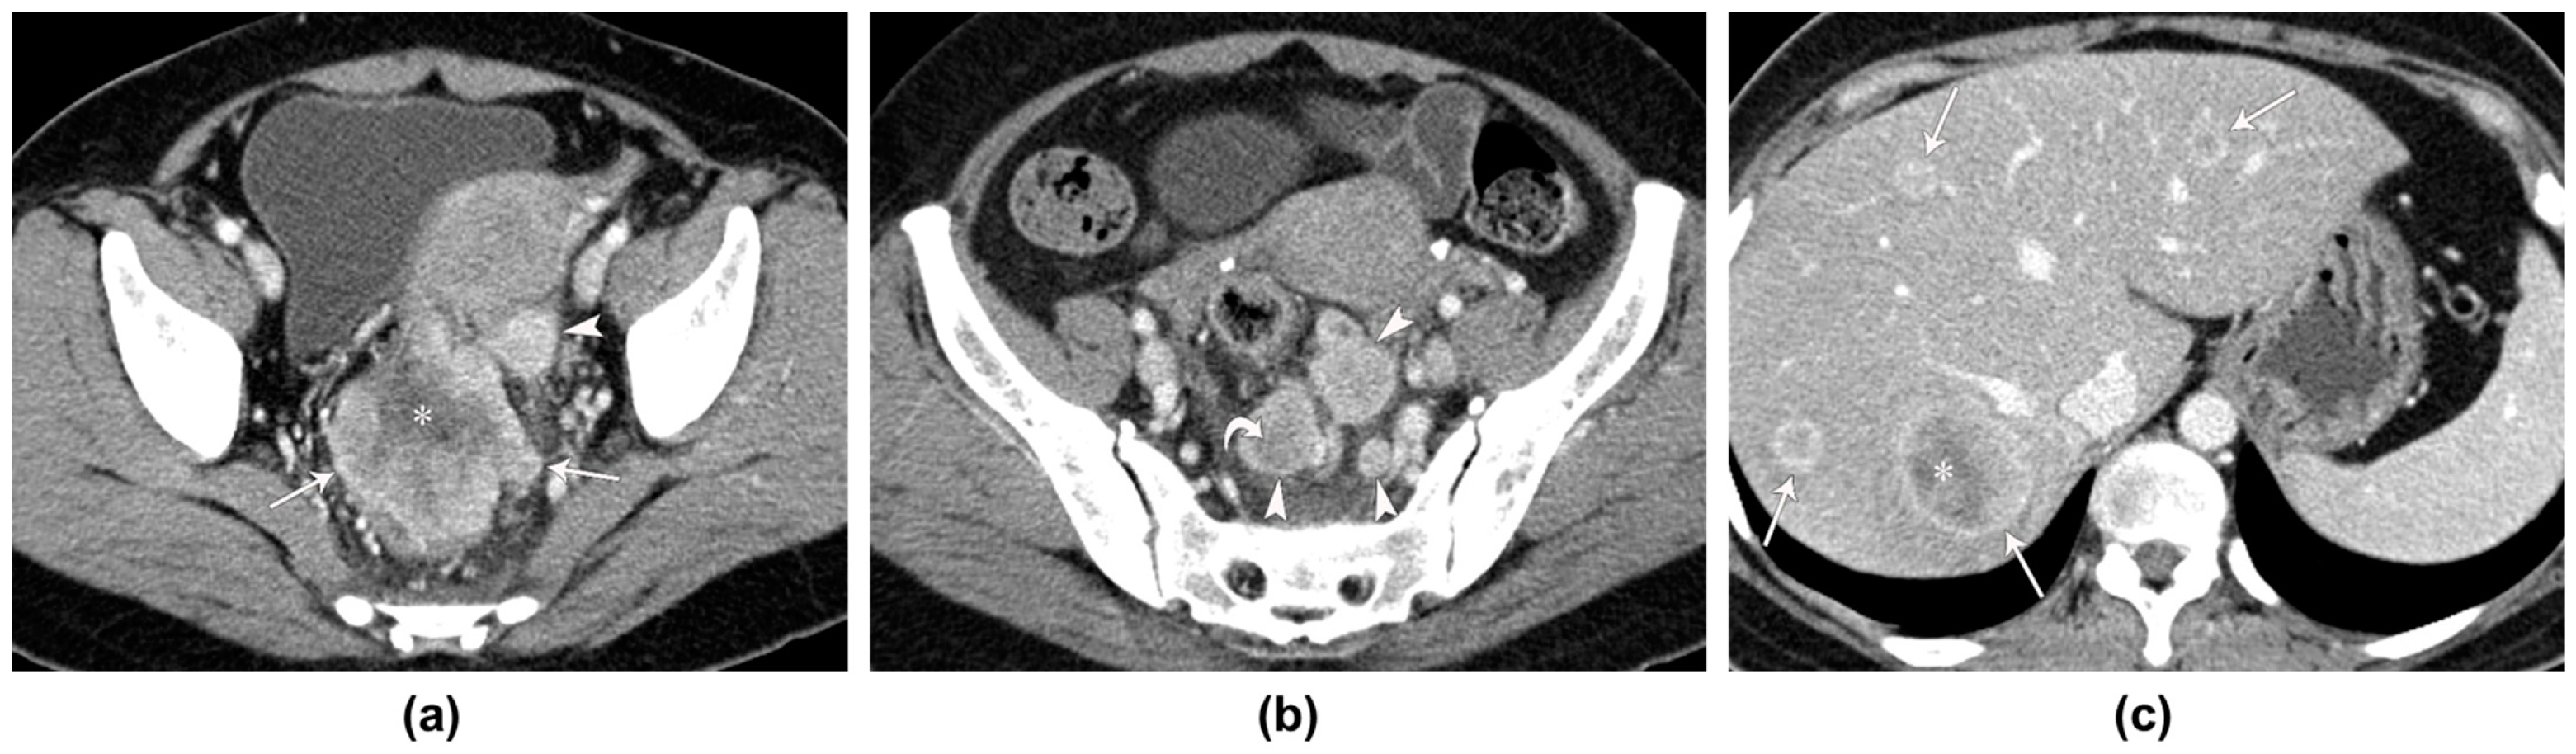

| 70/F | Abdominal pain | CT, US | Sigmoid colon | Bulky mass | 44 | Heterogeneous | Well (3.01) | Yes | 0/NA | NA | Right ureter and ovary, ileum, urinary bladder, iliopsoas muscle, and uterus | No |

| 54/F | Fever | CT, US, PET-CT | Ra | Bulky mass | 49 | Heterogeneous | Well (2.02) | Yes | 8/21 | Yes | Uterus | Liver |